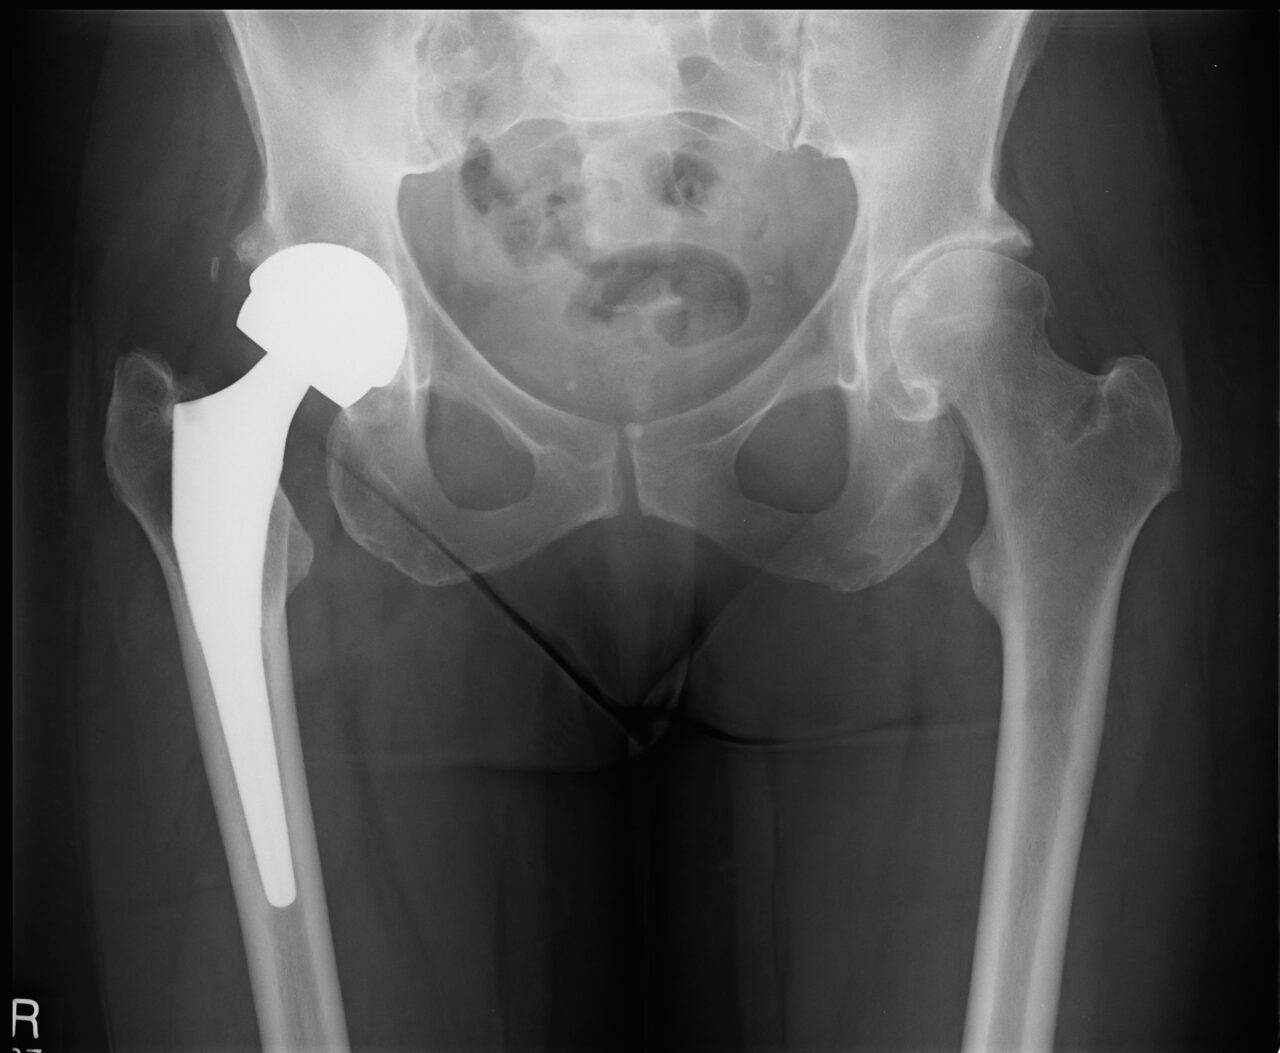

Joint Replacement

Rothman Orthopaedics' Joint Replacement Program is one of the nation's top joint replacement centers, performing more than 17,000 joint surgeries annually.

Because like all surgeries, joint replacement procedures do require some recovery time, they are normally only considered after all other non-surgical options have been discussed and/or attempted. Normally, joint surgery provides significant and wonderful results for the majority of patients. At Rothman Orthopaedic Institute, patients have the advantage of being seen by physicians who have actually helped develop and launch joint replacement techniques and who are considered to be well-renowned authorities on the topic of joint replacement

The joint replacement team at Rothman Orthopaedic Institute performs more than 9,000 surgeries every year. Each member of the team is specially trained, has extensive experience and is skilled to perform total joint replacements. Every physician that is a part of this outstanding team of doctors has undergone extensive subspecialty training during his/her residency and fellowship. This team is at the cutting edge of new research in the joint replacement field and Rothman physicians are actually responsible for training other orthopaedic surgeons through international lectures, webcasts, and surgical satellite simulcasts.

Is it right for you?

If you experience pain in any of your joints due to physical activities such as walking, running, and climbing stairs, it may be time to have a Rothman Orthopaedic Institute specialists diagnose your case. Joint replacement may be the answer for you. When simply sitting in a favorite chair or sleeping in your bed causes enough pain to wake you or make your life extremely uncomfortable, joint replacement may be able to get you back to an active lifestyle with less pain.